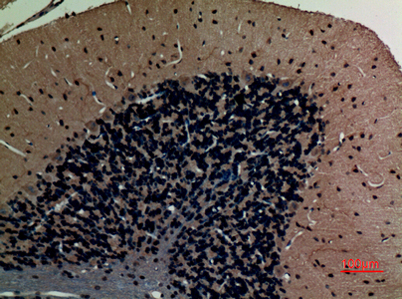

Product name: ABCG1 rabbit pAb

Dilutions: Western Blot: 1/500 - 1/2000. IHC-p: 1:100-300 ELISA: 1/10000. Not yet tested in other applications.

Immunogen: Synthesized peptide derived from ABCG1 . at AA range: 560-640